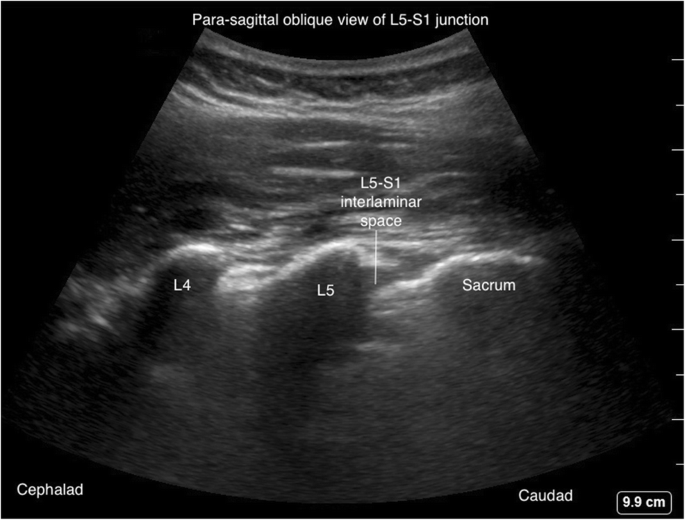

The para-sagittal scanning can be used for ascertaining the exact vertebral level before the procedure. In this method, the ultrasound transducer is placed over the sacrum to identify the L5 transverse process and L5–S1 intervertebral space (Figs. 8 and 9). The transducer is then slid cranially to identify the respective L5–L4, L4–L3, and L3–L2 interspaces.

para-sagittal scanning은

시술 전 정확한 척추 수준을 확인하는 데 사용될 수 있습니다.

이 방법에서 초음파 트랜스듀서는 천골 위에 배치되어

L5 횡돌기와 L5–S1 척추간 공간을 식별합니다(그림 8 및 9).

L5–S1 intervertebral space

그 다음 트랜스듀서를 두개골 방향으로 이동시켜 각각의 L5–L4, L4–L3, 및 L3–L2 간공간을 식별합니다.

Fig 9

Para-sagittal oblique view of L5-S1 interlaminar space